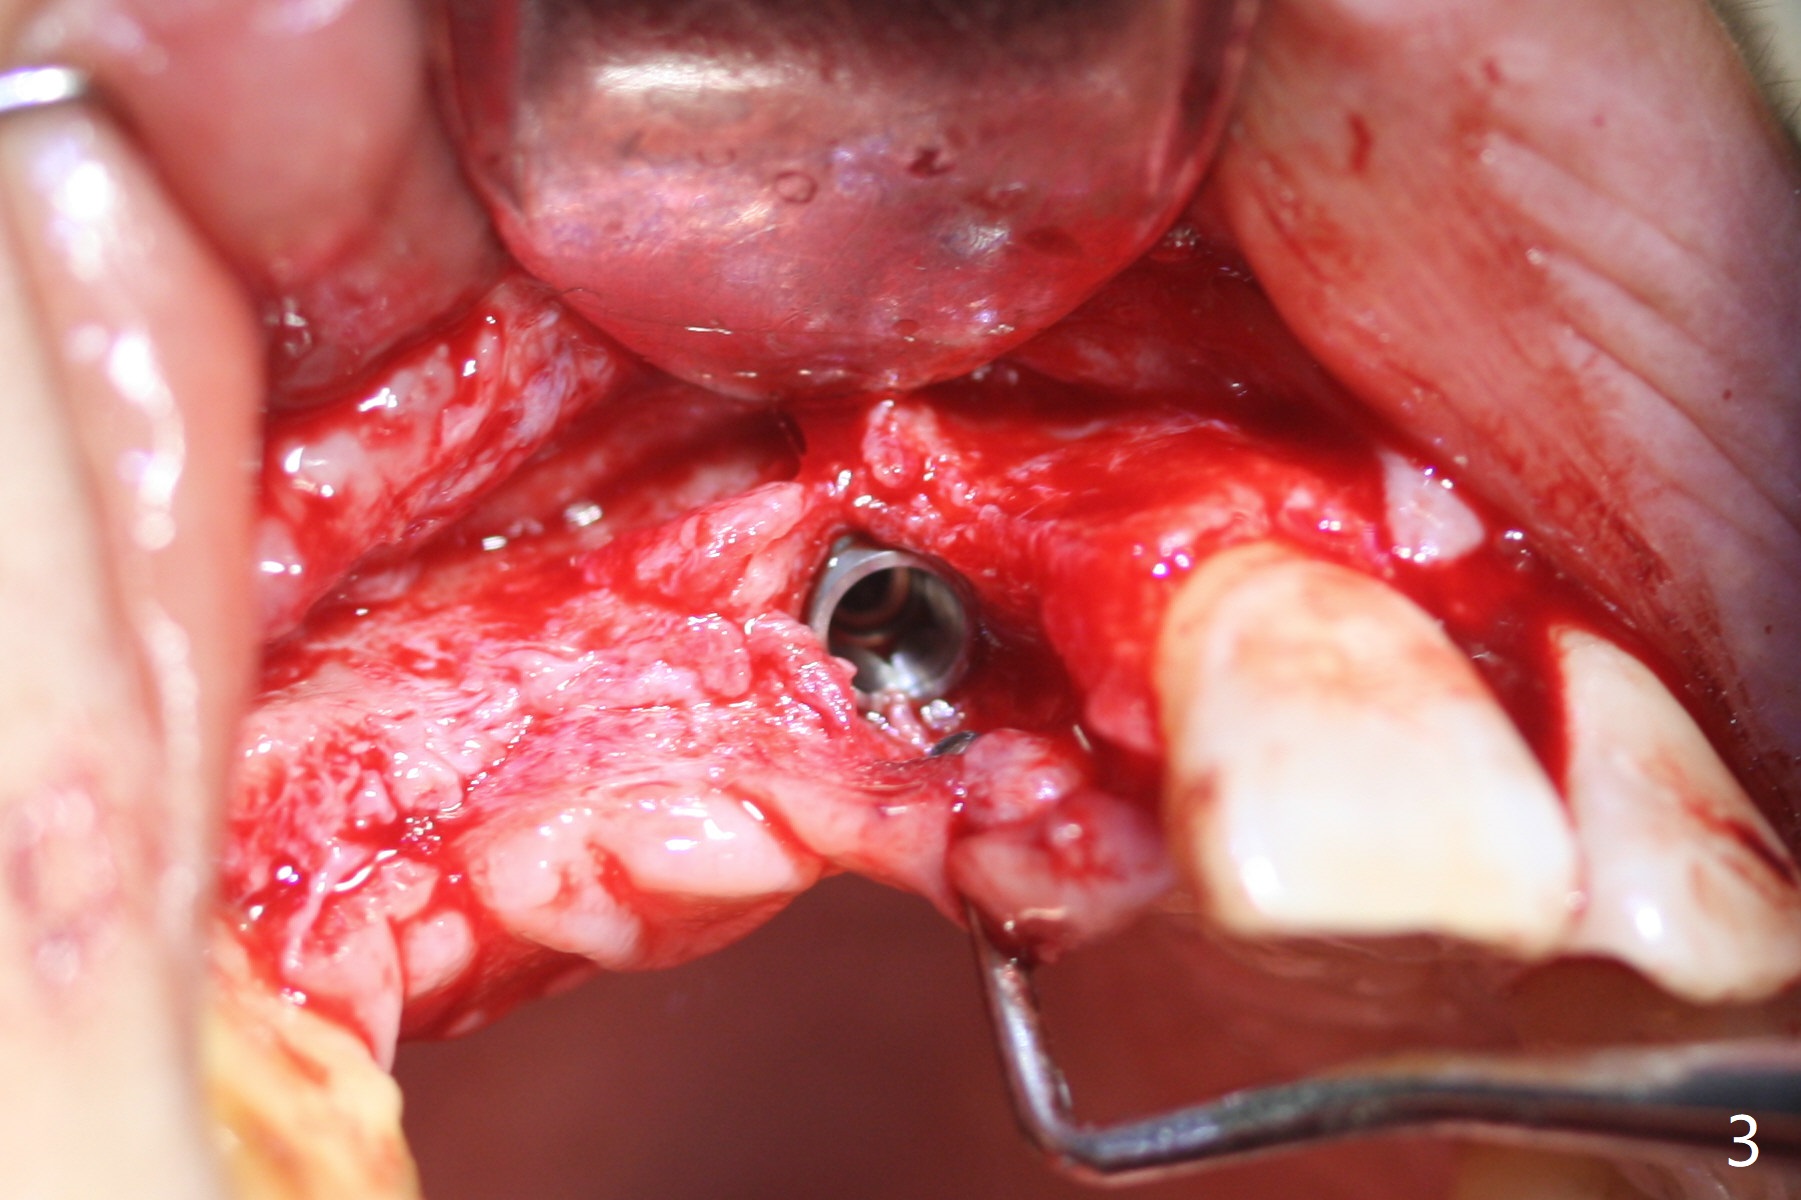

Eleven months post immediate implantation, the implant at #8 (4.5x16 mm, better smaller) is found to have thread exposure buccally (Fig.1) and distally (Fig.2). Immediately post implant removal, a 5x10 mm one is placed equi- or subcrestally distobuccally (Fig.3,4 (to prevent periimplantitis)). It is turned 4 more times later to make sure slightly supracrestally palatally, since the palatal crest is the lowest. After placement of sticky bone palatally, a 4.5(2) mm mill abutment is placed (17 mm long, Fig.5,6). The buccal flap is raised until the anterior nasal (Fig.5 N) foramen. After severing the periosteum and placement of 2 of 8 mm tenting screws (Fig.7), sticky bone (Vanilla allograft/Osteogen; block graft denies) is applied at #6 and 7 sites (Fig.8). Following palatal flap separation, the wound is closed in an apparent tension free manner (Fig.9). Periodontal dressing is applied. After wound healing, lab-fabricated provisional is delivered.